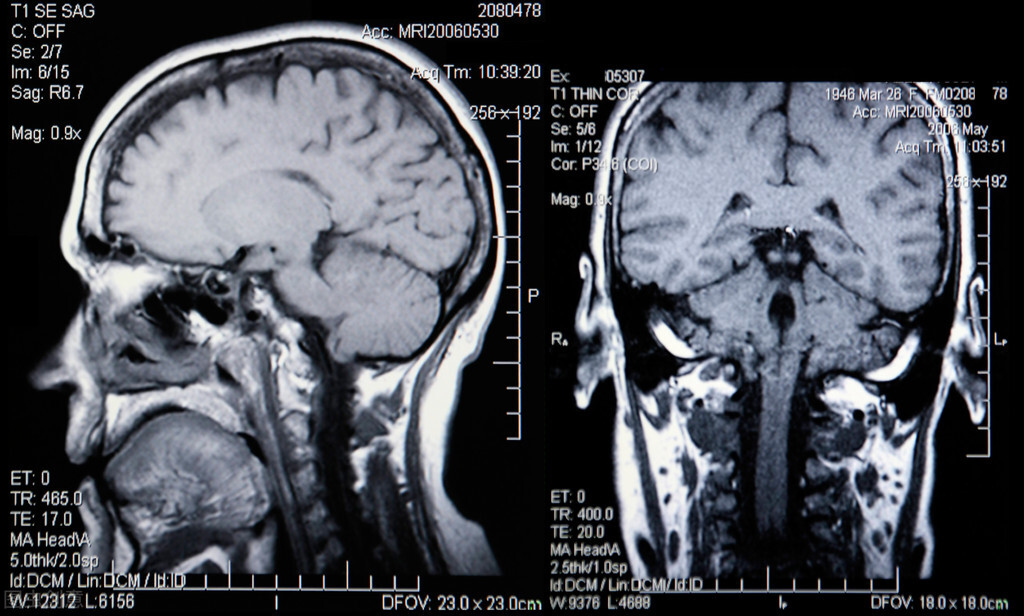

后来,他去医院做了核磁共振,结果发现他脑子中的水库出现了漏水的现象,专业的名称就叫做脑脊液漏。

我们的身体每天能够产生400到500毫升左右的脑脊液,正是因为这些脑脊液的保护,才使得我们的大脑在受到外部撞击的时候有一定的缓冲力,能够保护我们的大脑。

但是当大脑中的这些脑脊液漏出的时候,脑脊液量就会减少,那么保护我们大脑的水库就会消失,大脑直接和颅骨接触就很容易受到伤害。

那么为什么大脑会漏水呢?因为脑脊液不仅仅是在大脑中循环,还会循环到腰椎到脊髓里面,然后再回收到脑子里。在这个循环过程中,任何一个环节出了问题,回收到脑子中的脑脊液就不会那么多了。水库中的水就减少了。一旦脑脊液漏水,人体产生的脑脊液无法完全地补上水分,那么就会出现一系列的脑脊液漏的现象。